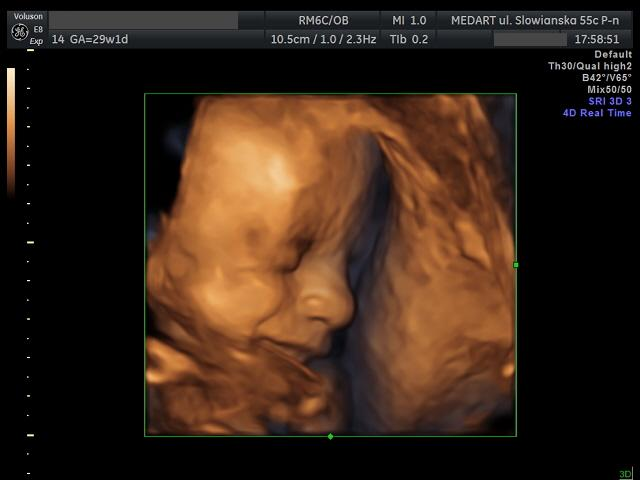

Ultrasonografia trójwymiarowa (3D/4D)

• umożliwia obrazowanie trójwymiarowe płodu w czasie rzeczywistym

• optymalny czas wykonania badania to wiek ciążowy począwszy od 28 tygodnia ciąży

• badania wykonywane są przy użyciu aparatu Voluson E8 Expert firmy General Electric, zaopatrzonego w głowicę matrycowa RM6C

• oprócz wizualizacji dziecka za pomocą techniki 3D/4D przeprowadzana jest również ocena rozwoju płodu według schematu przyjętego dla badania przeprowadzanego pomiędzy 28 a 32 tygodniem ciąży (pacjentka otrzymuje oprócz nagrania i zdjęć również opis badania ultrasonograficznego)

• w wybranych sytuacjach klinicznych możliwe jest zastosowanie dostępnego w Ośrodku sprzętu ultrasonograficznego do trójwymiarowej wizualizacji i archiwizacji wybranych struktur płodu, a następnie analizy off-line; zgodnie z obowiązującymi rekomendacjami podstawą oceny anatomii płodu jest badanie wykonywane w prezentacji 2D